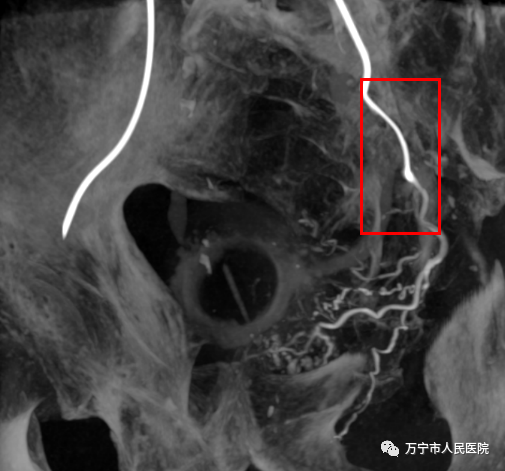

术中行C臂CT扫描证实插管位置正确(红色线框区域)